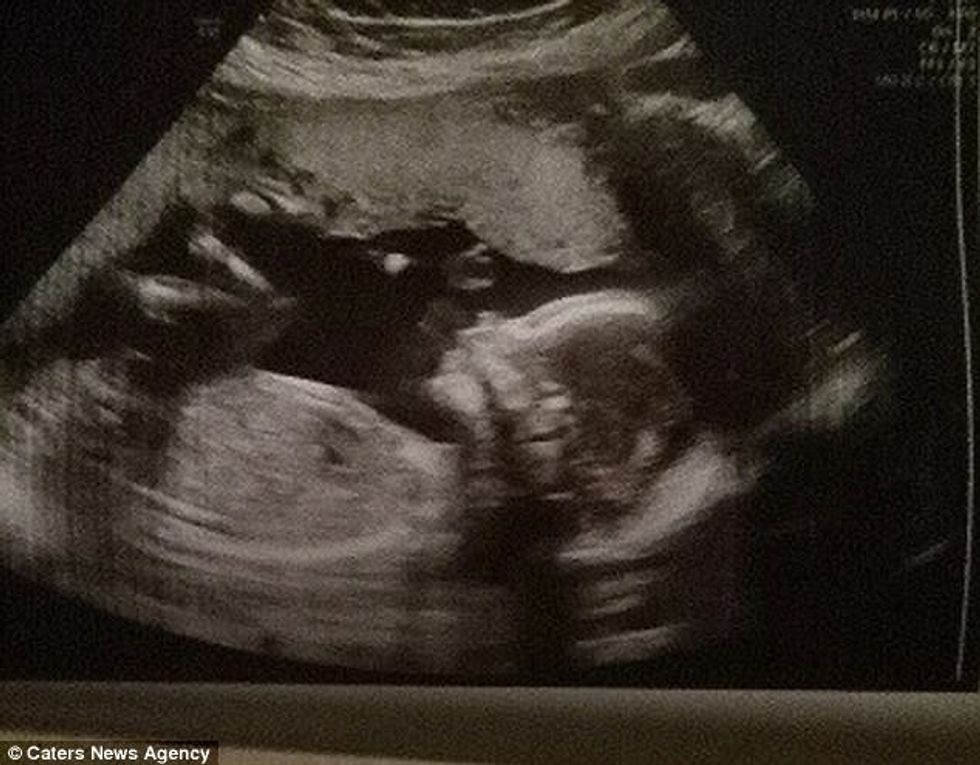

Ajo tani është në muajin e pestë të shtatzënisë, dhe po pret të sjellë në jetë një djalë.